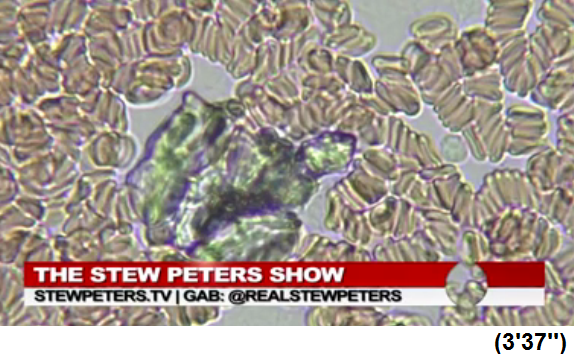

GENgeimpfte Menschen mit schweren

Nebenwirkungen in Südafrika 6.10.2021: Gestapelte

Blutzellen und schwarze Strukturen im Blut - Ärztin Zandre

Botha:

Purer Horror: Arzt entdeckt mysteriöse „schwarze

Strukturen“ im Blut von geimpften Patienten

https://uncutnews.ch/purer-horror-arzt-entdeckt-mysterioese-schwarze-strukturen-im-blut-von-geimpften-patienten/

Video auf Rumble (4.Okt.2021): https://rumble.com/vnbgal-never-before-seen-blood-doctor-reveals-horrific-findings-after-examining-vi.html

Video auf Bitchute (6.Okt.2021): https://www.bitchute.com/video/Sffxfn2Q7RGA/

Video auf VK (7.Okt. 2021): https://vk.com/video472868156_456239639

Video auf GloriaTV (5.Okt.2021): https://gloria.tv/post/CYb3Qraejiiy2SRLNkusqEjaC

Immer mehr Patienten der südafrikanischen Ärztin Zandre

Botha leiden nach der Corona-Impfung unter

Nebenwirkungen. Dazu gehören Thrombosen, Embolien,

kognitive Probleme, Nervenschmerzen und Kurzatmigkeit.

Sie beschloss, das Blut ihrer Patienten unter dem

Mikroskop zu untersuchen und war schockiert.

Die roten Blutkörperchen der Geimpften seien bis zur

Unkenntlichkeit deformiert, sagte Dr. Botha in der Stew

Peters Show. „Das habe ich noch nie gesehen. Ich war

schockiert“, sagte die Ärztin, die seit 15 Jahren in

diesem Bereich tätig ist.

Schwarze Strukturen

Außerdem fand sie bei allen geimpften Patienten mit

Symptomen „schwarze Strukturen“ im Blut. „Ich war sehr

schockiert“, sagte sie.

Botha gelang es auch, einen Janssen-Impfstoff in die

Hände zu bekommen und dessen Inhalt unter dem Mikroskop zu

untersuchen. „Ich war sehr schockiert, denn was ich im

Blut meiner Patienten fand, war auch im Impfstoff

enthalten“, sagte sie. Sie bezog sich auf die schwarze

Substanz, die aus zahlreichen Scheiben mit Löchern

besteht.

Der Arzt entdeckte auch seltsame rechteckige Strukturen

in dem Impfstoff. „Ich weine, wenn ich solche Dinge sehe.

Ich weine, wenn diese Patienten reinkommen“. Sie sagte,

einer ihrer Patienten habe innerhalb von fünf Stunden nach

der Impfung acht Herzinfarkte erlitten und liege nun auf

der Intensivstation. „Ich hoffe, ich kann ihm helfen.“

Letzte Woche wurde der Beipackzettel für den Impfstoff

Corona von Janssen um den Hinweis auf eine venöse

Thrombose, ein Blutgerinnsel in einer Vene, ergänzt.

Dr. Zandre Botha in Südafrika entdeckt das zerstörte Blut

der GENgeimpften mit schweren Symptomen und schwarzen

Objekten drin [17]

Südafrika: Ärztin Zandre Botha: Hier sind intakte

Blutzellen wie Billardkugeln [13] - Südafrika: Ärztin

Zandre Botha: Blutzellen sind gestapelt und bilden

Thrombosen [14]

Südafrika: Ärztin Zandre Botha: Schwarzes Objekt wie eine

Schildkröte im Blut [15] - Südafrika: Ärztin Zandre Botha:

Schwarzes Objekt wie ein schwarzes Wildschwein im Blut

[16]